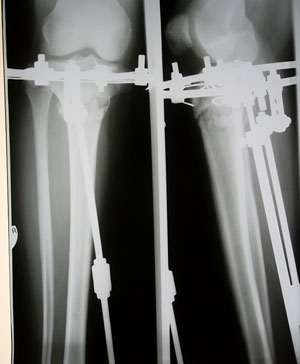

Костная мозоль зреет хорошо, к концу месяца можно приезжать на снятие аппаратов.

У Вас по 2 спицы в каждом кольце осталось???

Да, у меня на каждой ноге по две спицы, я хорошо себя чувствую, легче двигаюсь и намного легче поднимаюсь по лестнице))))

Чувствую себя хорошо, в общем у меня ломались спицы 6 раз, шестой раз было на 79 день со дня операций...осталось так же по 2 спице на верхней части аппарата)))) Скоро наступит день снятия УРРА!!!